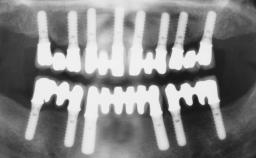

A healthy 31-year-old female patient presented with a failing maxillary left lateral incisor crown. The crown regularly loosened, and the remaining tooth was neither restorable nor rational to treat. The patient had a high smile line, a medium soft tissue biotype with a compromised mesial papilla (shorter than the contralateral one), and a horizontal scar in the buccal soft tissue as a result of past periapical surgery.

| Timing of placement | Immediate Placement (extraction sockets) (Type I) |

| Available apical bone to achieve primary stability | Sufficient height ( ≥ 4 mm) and width (> 2 mm around apex of planned implant) |

| Socket walls | Intact |

| Thickness of buccal wall | less than 2 mm |

| Anticipated residual defect after implant placement | 2 mm or less |